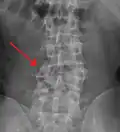

Burst fracture

A burst fracture is a type of traumatic spinal injury in which a vertebra breaks from a high-energy axial load (e.g., traffic collisions or falls from a great height or high speed, and some kinds of seizures), with shards of vertebra penetrating surrounding tissues and sometimes the spinal canal.[1] The burst fracture is categorized by the "severity of the deformity, the severity of (spinal) canal compromise, the degree of loss of vertebral body height, and the degree of neurologic deficit."[2] Burst fractures are considered more severe than compression fractures because long-term neurological damage can follow. The neurologic deficits can reach their full extent immediately, or can progress for a prolonged time.